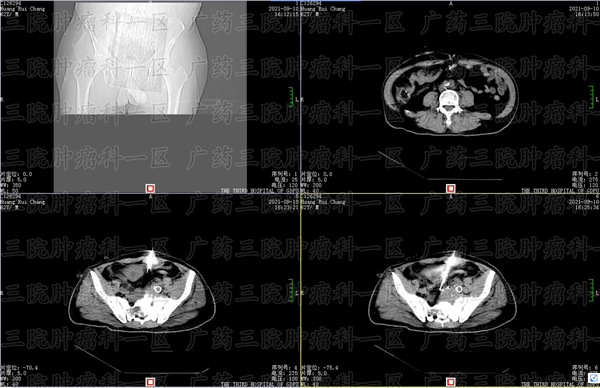

在医院检查,医生说发现了直肠壁异常增厚、直肠占位性病变,这是直肠癌吗?在医生建议下,患者进行了 进一步检查,最后确诊了直肠癌。那么,直肠占位病变真的是直肠癌吗?广药三院彭齐荣教授认为,不能这么说。

虽然这位患者查出直肠癌占位性病变后,确实被确诊为直肠恶性肿瘤,但彭齐荣教授指出,直肠占位性病变并不一定就等同于直肠癌。彭齐荣教授说,直肠占位不一定是癌症,直肠占位是指直肠或者直肠外有异常新生物,而导致肠腔变形的一种初步诊断。可能是良性肿瘤,也可能是恶性肿瘤,良性病变可能是直肠息肉,也可能是直肠腺瘤或者直肠肌纤维瘤。

如果想要明确具体病情,需要进一步检查。彭齐荣教授建议,查出直肠占位性病变的患者,可以进行肠镜检查,进一步观察病变情况并提取病理活检,明确病理类型。如果明确是直肠恶性肿瘤的话,患者就可以到肿瘤综合医院进行专业治疗。